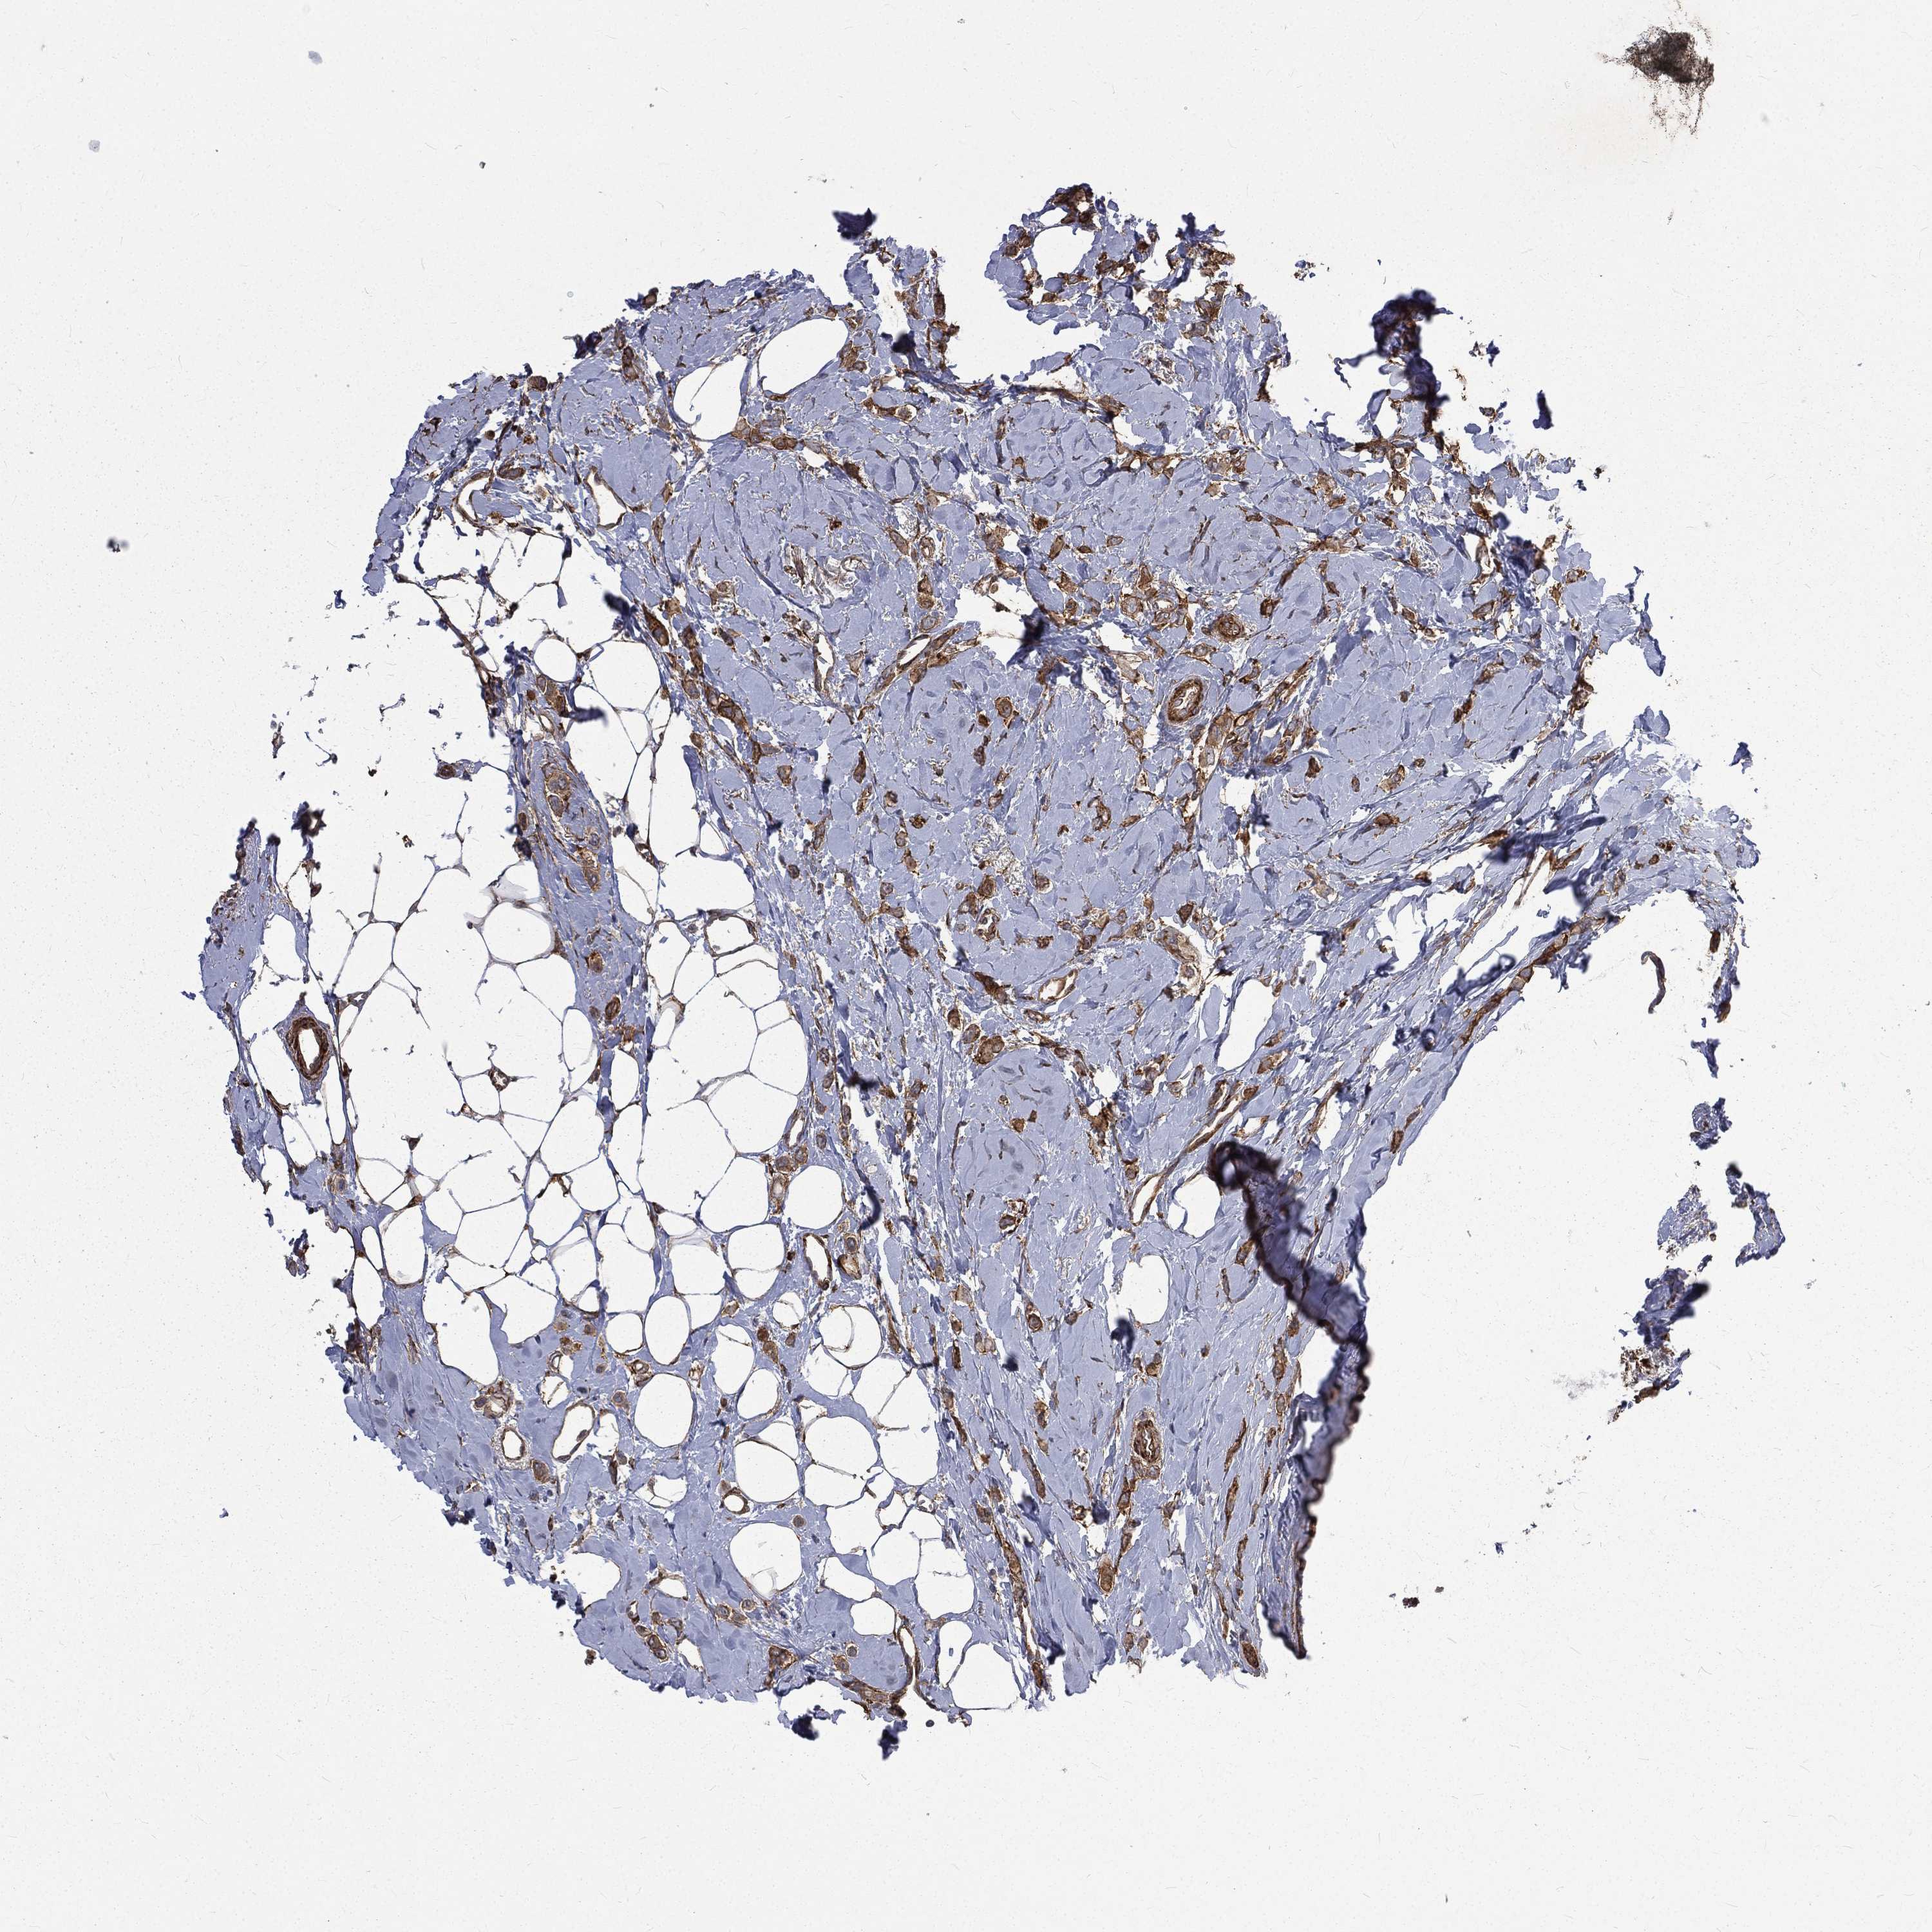

CANCER BREAST CANCER Show tissue menu

BRCA TCGA BRCA VALIDATION PROTEIN EXPRESSION

Breast cancer

Human cancer